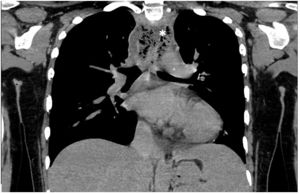

Paciente mujer de 17 años con antecedentes de meningoencefalitis en la infancia sin secuelas, que consultó por un cuadro clínico de una semana de evolución consistente en dolor cervical, odinofagia y fiebre de hasta 39°C. En la exploración física las constantes fueron estables, presentando dolor cervical a la movilización. En la analítica presentó elevación de reactantes de fase aguda. Se realizó una TAC cervical y torácica en la que se observó una gran colección cervical con abundantes burbujas de gas en su interior (figs. 1-3, asteriscos), con extensión hacia el mediastino posterior a través del espacio peligroso retrofaríngeo, hallazgos compatibles con fascitis necrosante y mediastinitis posterior. En las muestras quirúrgicas se cultivó Streptococcus dysgalactiae y S. intermedius. La paciente evolucionó favorablemente con tratamiento antibiótico y drenaje quirúrgico de la colección.